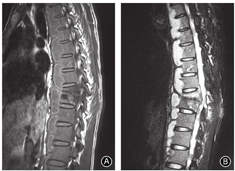

此外,脊柱结核更容易累及多个节段(图1),而化脓性脊柱炎往往局限在2个节段以内。Kim等[7]报告36.2%结核患者受累节段超过3个,而化脓性脊柱炎的比例仅为11.4%,故认为累及3个节段可作为支持结核诊断的重要依据。也有文献报道跳跃病灶现象支持脊柱结核的诊断,但缺乏其他研究的支持[6,9]。